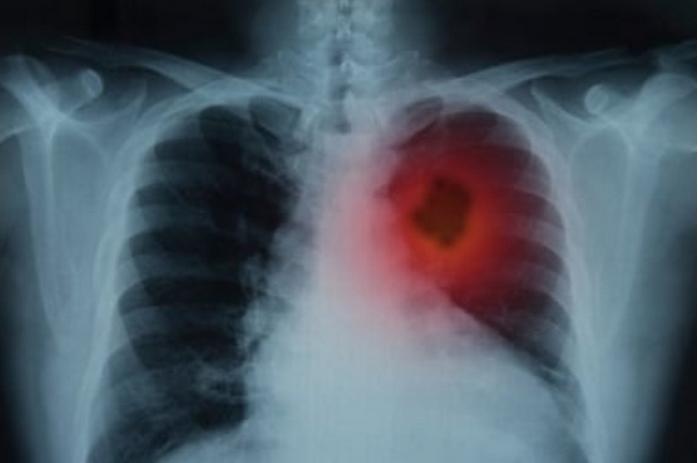

Kanker paru biasanya tanpa gejaa / Foto ilustrasi: Antara

JAKARTA, ARAHKITA.COM - Dokter Spesialis Paru dari Rumah Sakit Kanker (RSK) Dharmais, Jakarta dr Mariska Pangaribuan mengatakan 88 persen pasien kanker paru meninggal pada tahun yang sama pada saat kankernya ditemukan.

"Sekitar 88 persen pasien kanker paru yang ditemukan akan meninggal pada tahun yang sama. Kanker paru merupakan penyebab kematian tertinggi pada pasien kanker," katanya dalam diskusi mengenai kanker paru yang diikuti secara daring di Jakarta, Kamis (29/2/2024).

Tingginya angka kematian pada pasien kanker paru, menurut Mariska disebabkan keterlambatan kedatangan pasien untuk berobat. Pasien kanker paru baru berobat setelah berada dalam stadium lanjut. Hal itu terjadi karena jenis kanker yang satu ini tidak menunjukan gejala awal.

"Kalau gejalanya sudah muncul biasanya stadiumnya sudah lanjut atau seringkali malah sel kanker sudah menyebar ke tempat lain yang menyebabkan gejala terlebih dahulu," ucapnya.